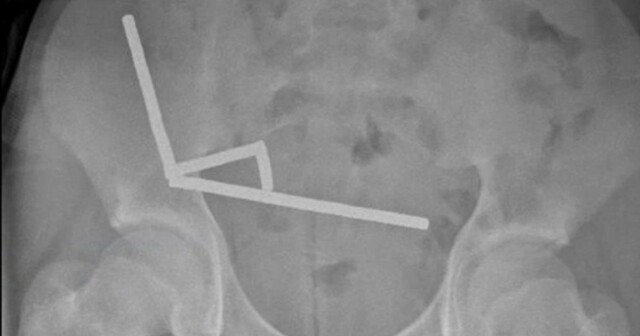

Хирурги были поражены, обнаружив, что причина болей в животе у подростка — более ста мощных магнитов. В результате врачи новозеландской больницы в Тауранге провели экстренную операцию и удалили часть кишечника 13-летнего пациента.